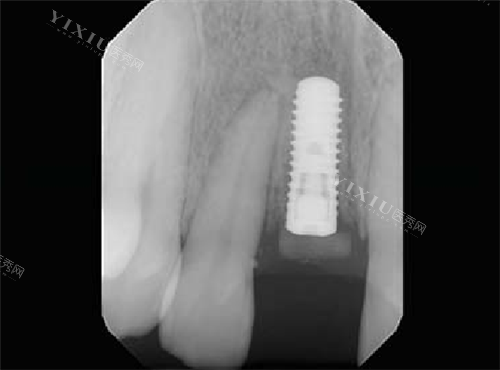

接着就是一系列的常规检查,要拍片对我的骨质进行测量和评估,确定打算植入的种植体规格。医生跟我说,每个人的口腔状况都不一样,所以得根据我的具体情况来选合适的种植体。检查的时候,医生特别仔细,一边检查一边跟我解释各项检查的目的,让我心里踏实了不少。

种植牙的过程分为好几个步骤,先把种植体植入,接着装上基台,然后装上牙冠。手术过程中,我虽然感觉不到疼,但能感觉到医生在我嘴里操作,心里还是有点忐忑。不过医生的技术特别好,操作很熟练,整个过程也比较顺利。